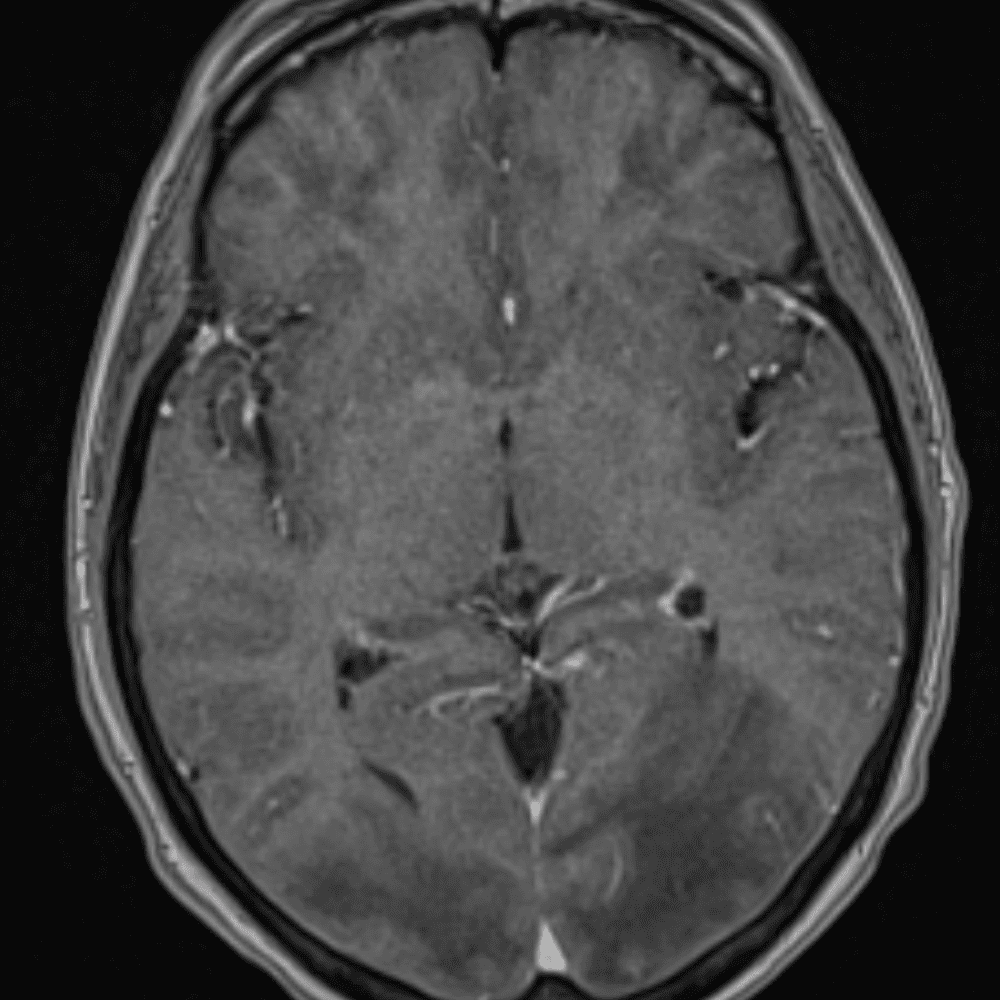

๋‹น์ง ์‹œ ํ”ํžˆ ๋ณผ ์ˆ˜ ์žˆ๋Š” ์‚ฌ๋ก€์˜ ์ „ํ˜•์ ์ธ ์˜ˆ๋ฅผ ํฌํ•จํ•ฉ๋‹ˆ๋‹ค.

39 ์‚ฌ๋ก€

์—ฐ์Šต

๋ฏธ๋ฌ˜ํ•˜๊ฑฐ๋‚˜ ์–ด๋ ค์šด ์‚ฌ๋ก€์™€ ์ผ๋ถ€ ์ •์ƒ ์‚ฌ๋ก€๋ฅผ ํฌํ•จํ•˜์—ฌ ๋‹น์ง์„ ์‹œ๋ฎฌ๋ ˆ์ด์…˜ํ•ฉ๋‹ˆ๋‹ค.

50 ์‚ฌ๋ก€